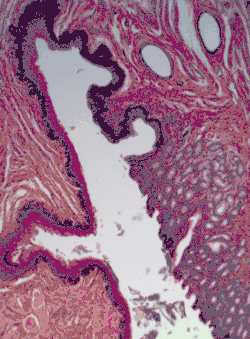

Non-keratinized stratified squamous epithelium, image highlights the epithelial nucleuses, rest of the epithelial layer, underlying connective tissue and other epithelia